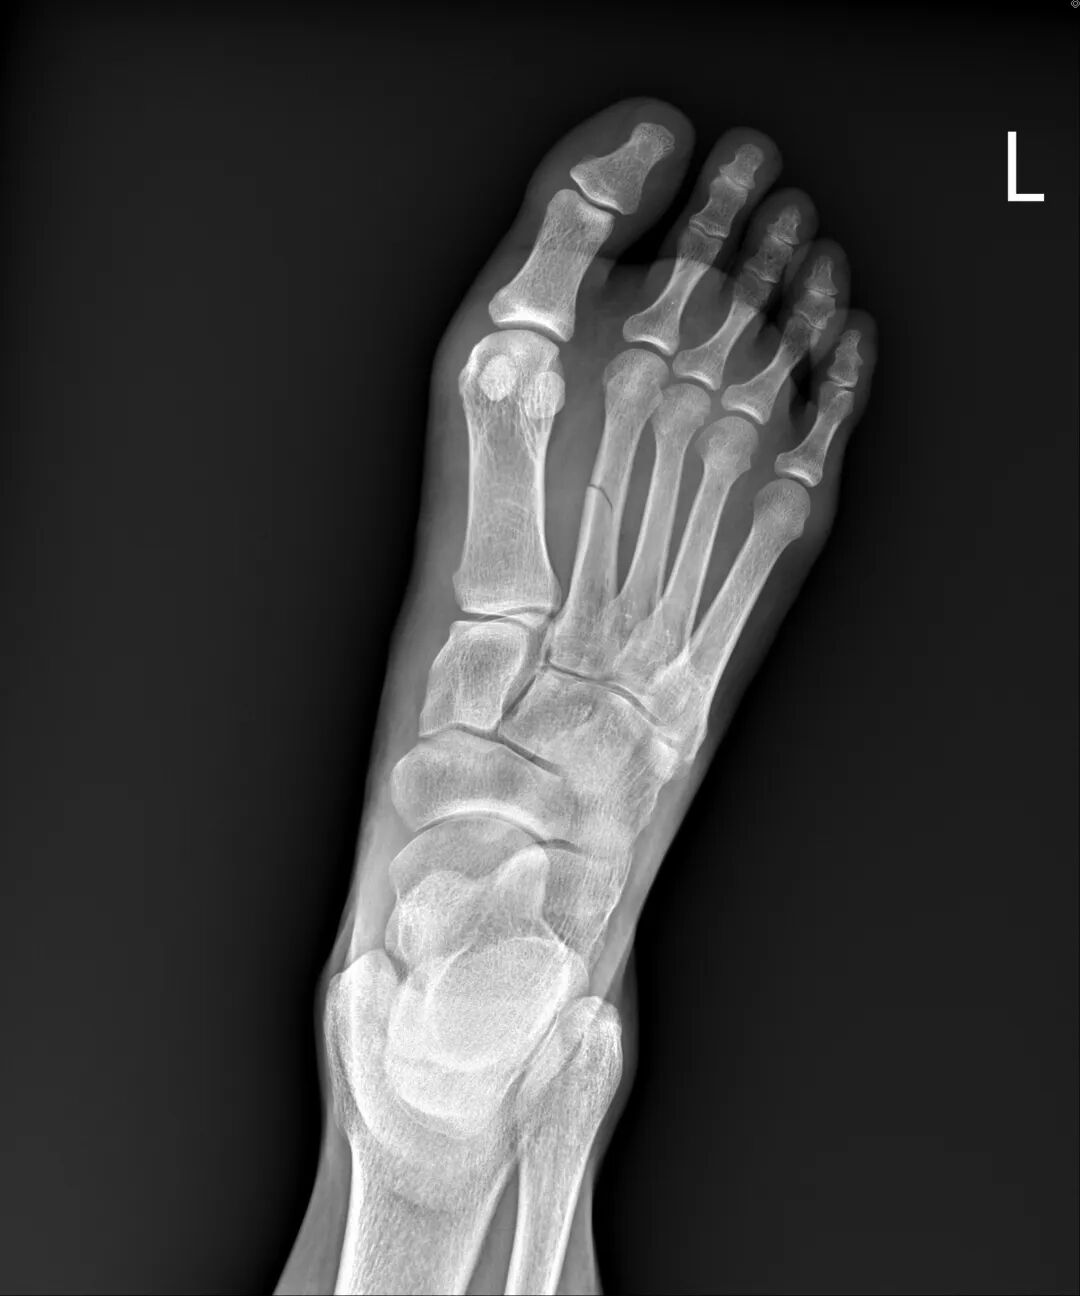

“这是骨折变形了。”

后来看到我的病历上写到,据EMT表示患者为机汽车事故,有着安全帽,到场时患者趴在地。左小腿触痛、肿胀、变形。不记得车祸发生路线,疑似失去意识。

茫然地望着天花板的日光灯。刚刚发生了什么事,我怎么想也想不起来,抬头看着剧烈疼痛、变形的左小腿,脚背外缘瘫倒病床上。

我不知道有没有事,从车祸发生当下开始,只能静等医护人员安排。X光室门开启,变形小腿摆拍酷刑开始。从病床移动到摄影台,放射师用辅具帮小腿摆好几个不同拍摄角度。只要一点移动,就产生剧烈疼痛,我在心里重复默念:“痛,只是种感觉。”

医生告知诊断:小腿里两根骨头都断了,要用手术固定。小腿里有两根骨头,胫骨和腓骨。他们的排列像吃鸡翅时,掰开的那大小骨头。

姐姐国中同学刚好是骨科住院医生,特地过来关心,耐心地说明目前伤势,除了已知的小腿骨折外,他指着脚背说,这里也有骨折。

我马上说出骨头学名:跖骨,因为同一只脚第四根有断过。

复健科医生看到X光片后都说:“你这个很严重耶。”为了想尽快恢复生活,我积极去复健治疗。因长时间卧床,受伤腿肌肉严重萎缩,努力运动,抵挡肌肉流失的速度。